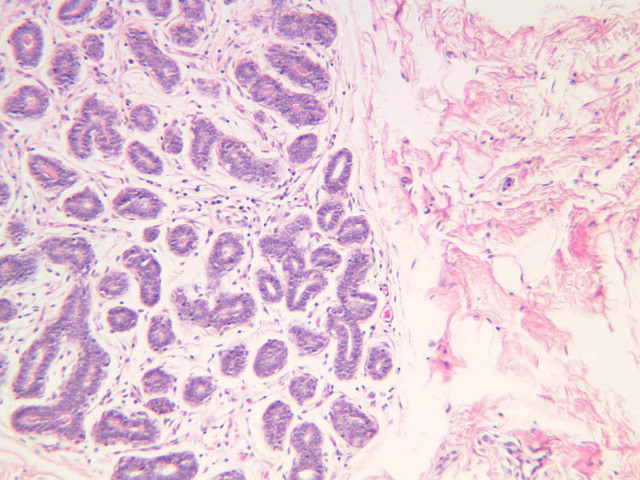

This phase occurs during days 7 to 14 and corresponds to the ovarian follicular phase with rising levels of estrogens. The functionalis layer is replaced by growth of the endometrial elements in the basalis. The glands are usually straight tubes extending from the surface. Epithelial cells become taller and accumulate glycogen basal to their nuclei. (slide B-93 [2.5x, 10x, 20x, 40x]; B-97 [2.5x, 10x, 20x, 40x])